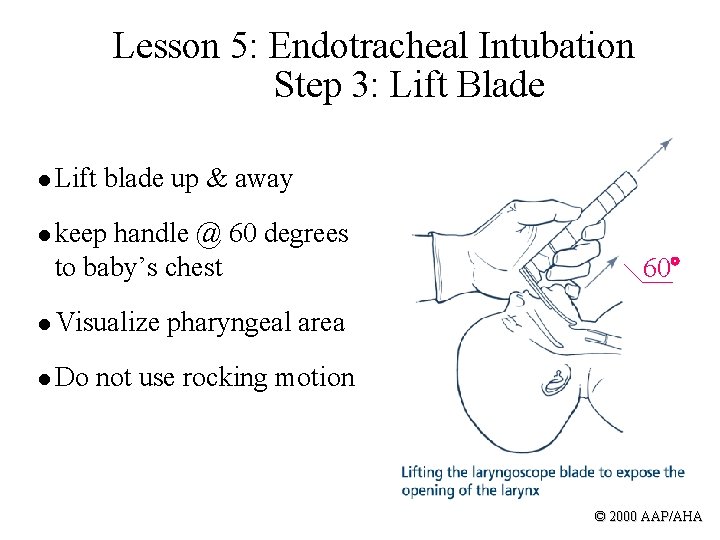

Lesson 5: Endotracheal Intubation Step 3: Lift Blade l Lift blade up & away l keep handle @ 60 degrees to baby’s chest 60 l Visualize pharyngeal area l Do not use rocking motion © 2000 AAP/AHA